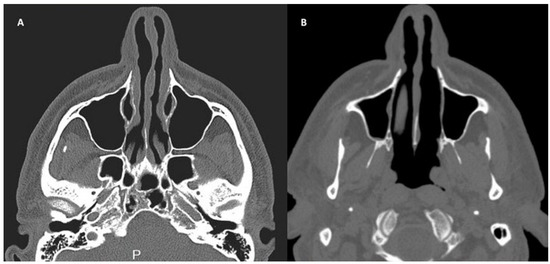

2.4. Patients and Clinical Procedure